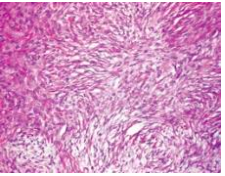

Storiform

Front

Having a cartwheel pattern - spindle cells with elongated nuclei radiating from a center point Cellular spindled lesion with whorls of cells as opposed to parallel fascicles or right angle bundles